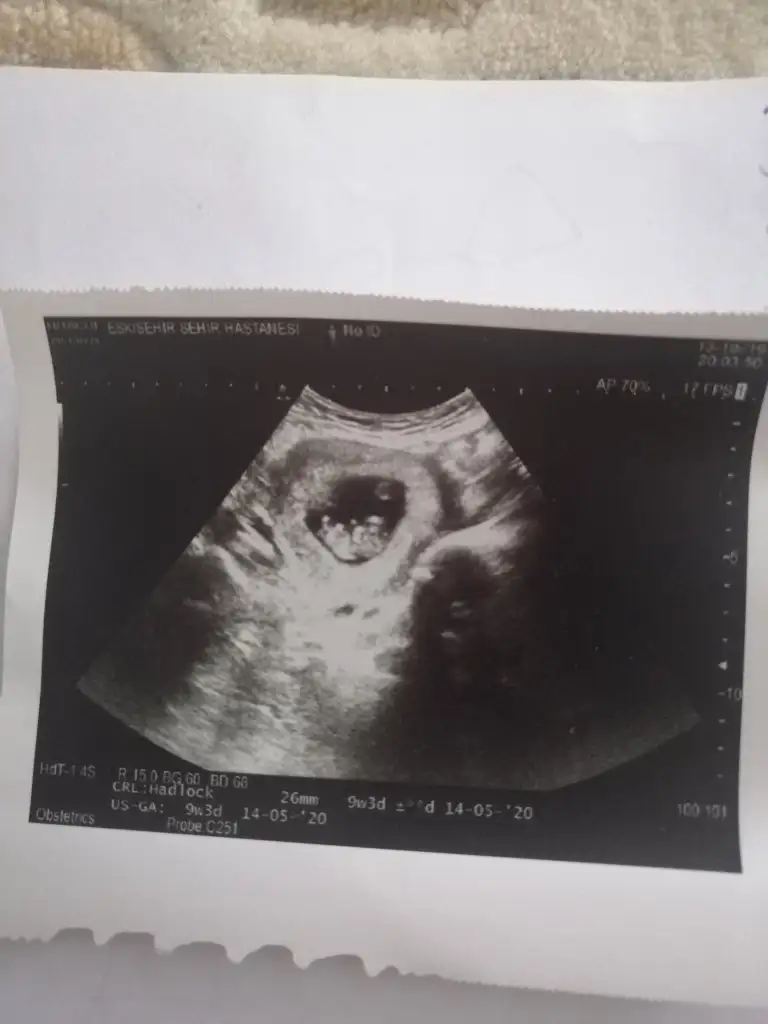

Banada erkek demiştiniz hatta baya net erkek demiştiniz kız diyince doktor şaşırmıştınız bnde çok şaşırmıştım tabi çünkü baya umutlanmıştım 2 kızım var doğal olarak değişik olsun istemiştim tabiki Rabbim in dediği olur ama hala erkek hissediyorum ayrıntılıda pozisyonu tersti cinsiyeti gözükmüyor demişti perinatolog ama 2 doktor kız gibi biride düşük kalitede bir cihazda kız demişti sonra rüyamda bebeğimin isminin koyulduğunu gördüm mavi nüfus kağıdında Ali arif yazıyordu bilemiyorum hala erkek hissediyorum pembe kıyafetleri almama rağmen

az kaldı sonucu görmeye herşey den önce Rabbim sağlıklı ve hayırlı evlatlar nasip etsin bizlere